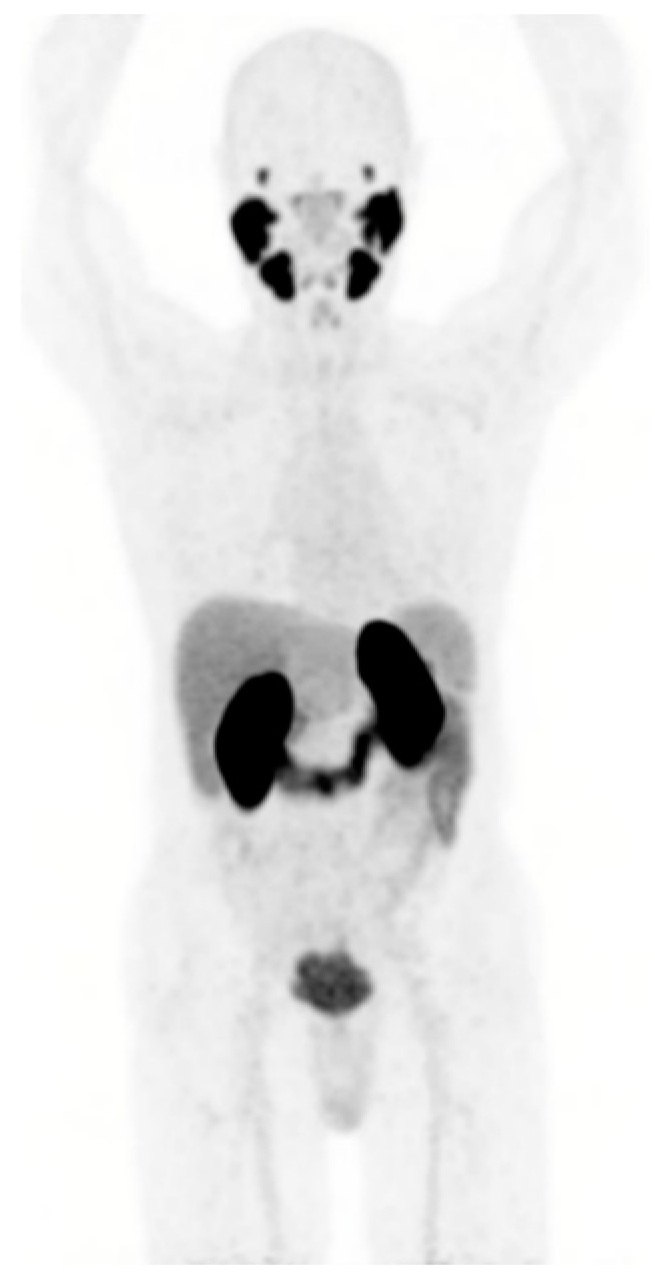

Prostate-specific membrane antigen (PSMA) is highly expressed on the membrane of most prostate cancer cells in correlation with Gleason score and castrate resistance status, and to a lesser extent in normal tissues (prostate, small intestine, salivary and lachrymal glands, and kidney) [10]. This explains the human physiological biodistribution of radiolabeled PSMA ligands used for PET imaging (PSMA PET) (Figure 1).

Figure 1. Physiological PSMA expression in normal tissues assessed by [68Ga]Ga-PSMA-11 PET performed at Lumen nuclear medicine department.